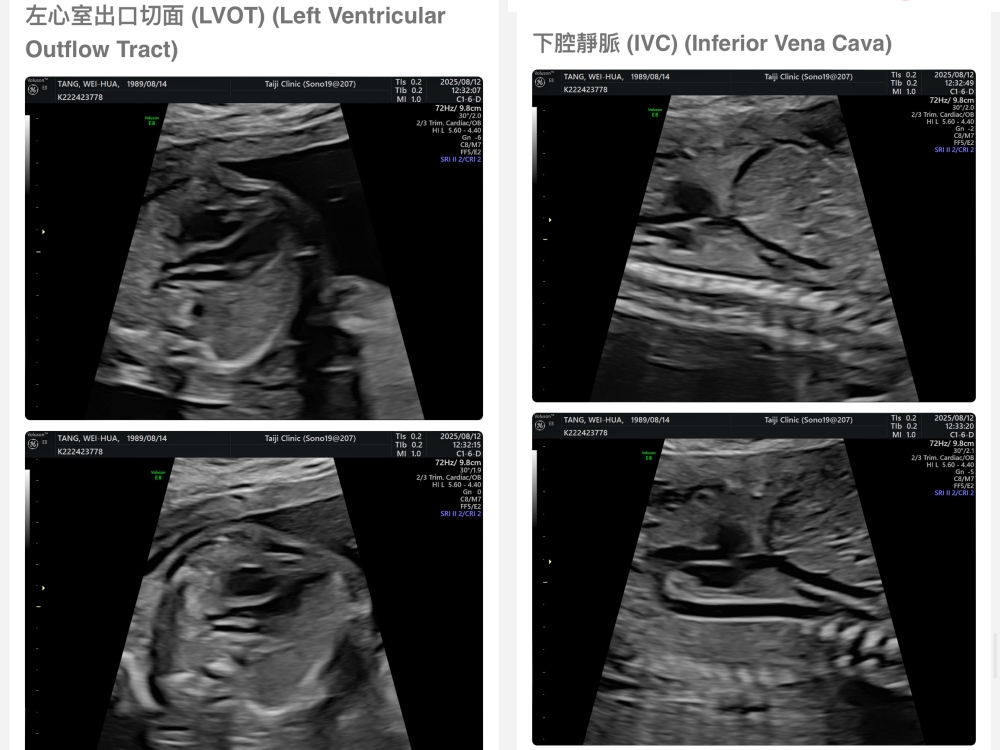

【台兒|高層次超音波|檢查結果】

▲離開診所後會收到MAIL,我們14:05離開,大約是16:45收到mail,裡面會有滿滿的超音波照片,紀錄的很詳細!也會提供紙本的報告,可以給日後產檢的醫師做參考👌